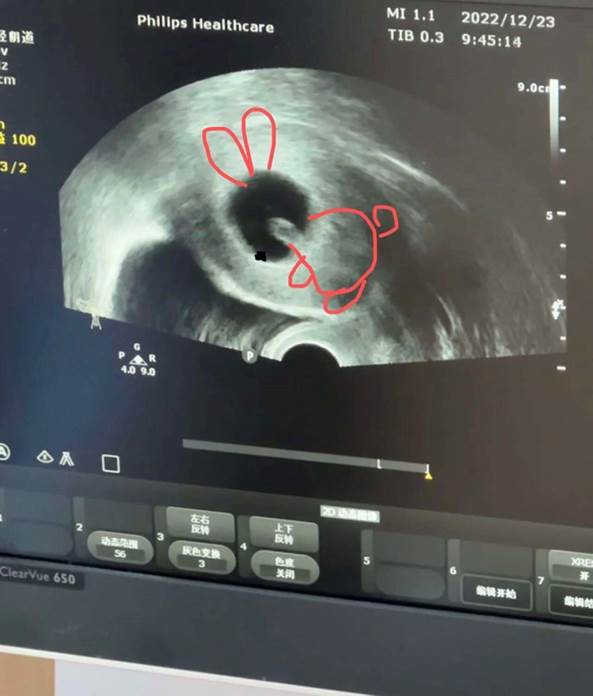

在验出怀孕的第五周,大鱼出现了下体流血的症状。在医院进行阴超检查后,医生发现大鱼的子宫内出现了出血点,积血块的大小超过了孕囊。为了保住她的第二个孩子,大鱼开始给自己注射肝素和生长激素。“也是在那个时候,我开始出现孕吐反应,每天都吐得很厉害。我以为我的宝宝长得很好,像在向我发出信号,妈妈我挺好的,你别担心。”大鱼的喜悦没有维持很久。怀孕第八周时,胎儿被检测出有胎芽、无胎心的状态,医生将其判定为胎停育,建议大鱼尽早终止妊娠。大鱼再一次失去了她的孩子。

大鱼一移胎停时的B超